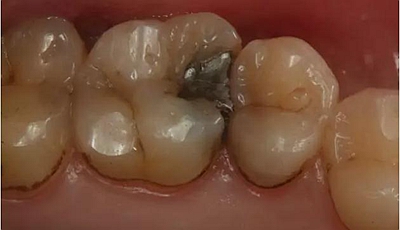

患者男性,35歲,B6銀汞充填后食物嵌塞,要求重新充填,口內(nèi)檢查見B6近中鄰頜面銀汞充填物,局部缺損,有繼發(fā)齲,去除原充填物及繼發(fā)齲,發(fā)現(xiàn)齲壞位于牙齦下方,給予冠延長(zhǎng)手術(shù),同期嵌體預(yù)備,后一次性取模。(同樣設(shè)計(jì)為齦上邊緣)

硅橡膠取模后,灌注模型,科爾琥珀樹脂制作嵌體。

一周后拆線,口內(nèi)試戴合適,粘結(jié)嵌體。